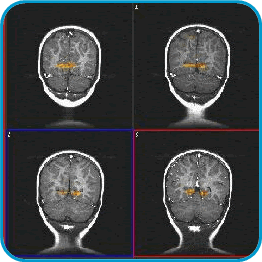

These images are from a 2 year-old child. They are named coronal cuts. The head is seen on top and the neck is on the bottom. Inside you see the two hemishpheres of the brain, and below them the cerebellum. The patient was sedated for a regular procedure. Flashing lights were presented during 3 minutes. The visual cortex, located in the occipital lobes, is depicted in red and yellow colors.

Images of activation in sedated kids have been obtained by presenting sounds (such as the mother's voice), or tactile stimulation to the skin (such as rubbing the hand).